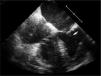

Transthoracic echocardiography (TTE) was performed in order to determine the cause of the patient's HF and to assess her cardiac function. This revealed findings compatible with hypertensive heart disease (left atrial dilatation, moderate left ventricular hypertrophy, mild mitral regurgitation and grade 2 diastolic dysfunction) and preserved biventricular systolic function, and also identified a mobile mass attached to the mitral valve leaflets. Transesophageal echocardiography (TEE) confirmed this mass to be a vegetation around 19 mm×4 mm in size, adhering to the atrial face of the posterior valve leaflet and highly mobile (Figure 1A and B).

Transesophageal echocardiography (TEE) showing nonbacterial thrombotic endocarditis. (A and B) Initial TEE showing a vegetation on the mitral valve posterior leaflet (arrow); (C) following a course of antibiotic therapy, the vegetation can still be observed on the mitral valve posterior leaflet (arrow) and a new vegetation around 10 mm in size has appeared attached to the chordae tendineae of the posterior leaflet (asterisk). AD: right atrium; AE: left atrium; VD: right ventricle; VE: left ventricle; VM: mitral valve.

After four weeks of therapy with ceftriaxone, TEE was repeated and showed persistence of the original vegetation and revealed the presence of another, smaller vegetation, around 10 mm in size, attached to the posterior mitral valve leaflet (Figure 1C).